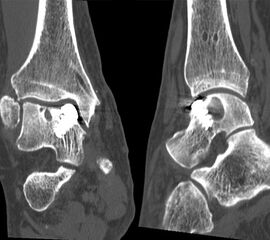

Der Computertomographie (CT) fehlt ebenfalls die Fähigkeit, den Knorpel direkt zu bewerten. Mit dem CT können jedoch weitere Details der knöchernen Verletzung, wie Größe, Form, Umfang und evtl. Dislokation der Läsion beurteilt werden 11. Insbesondere kleine Knochenkanten oder Gelenkkörper lassen sich in der CT wesentlich besser darstellen als mit einem MRT.

Zur Vollansicht und zum Lesen der Bildbeschreibung bitte das Bild anklicken.